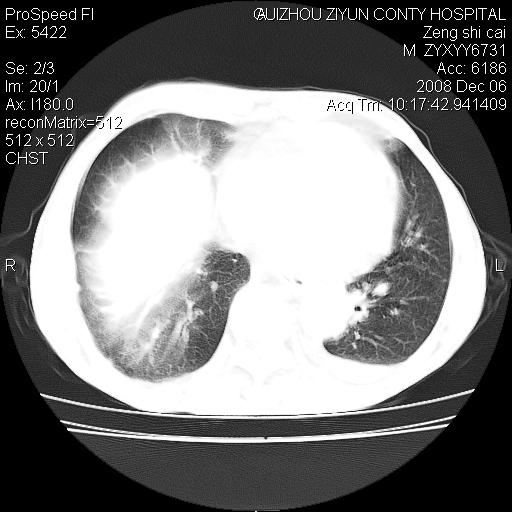

标题: CT16961:M、71岁,咳嗽半年,无血痰;胸片示右肺占位。 [打印本页]

标题: CT16961:M、71岁,咳嗽半年,无血痰;胸片示右肺占位。

右肺癌并纵隔淋巴结及胸膜转移可能性大

右肺癌并纵隔淋巴结及胸膜转移。建议气管镜

右肺纵隔型肺癌伴纵隔淋巴结及胸膜转移!

右肺纵隔型肺癌伴纵隔淋巴结转移!双侧胸水!

1)考虑右肺上叶纵隔型肺癌伴纵隔淋巴结转移。2)心包积液,双侧胸腔积液。

右肺癌并纵隔淋巴转移,腹膜后转移可能性大,两侧胸腔积液

右肺上叶纵隔型肺癌伴纵隔淋巴结转移。心包积液,双侧胸腔积液。

右上肺癌并纵隔淋巴结及胸膜转移。

右肺纵隔型肺癌伴纵隔淋巴结转移!双侧胸水\\心包积液

右肺纵隔型肺癌伴纵隔淋巴结及胸膜转移